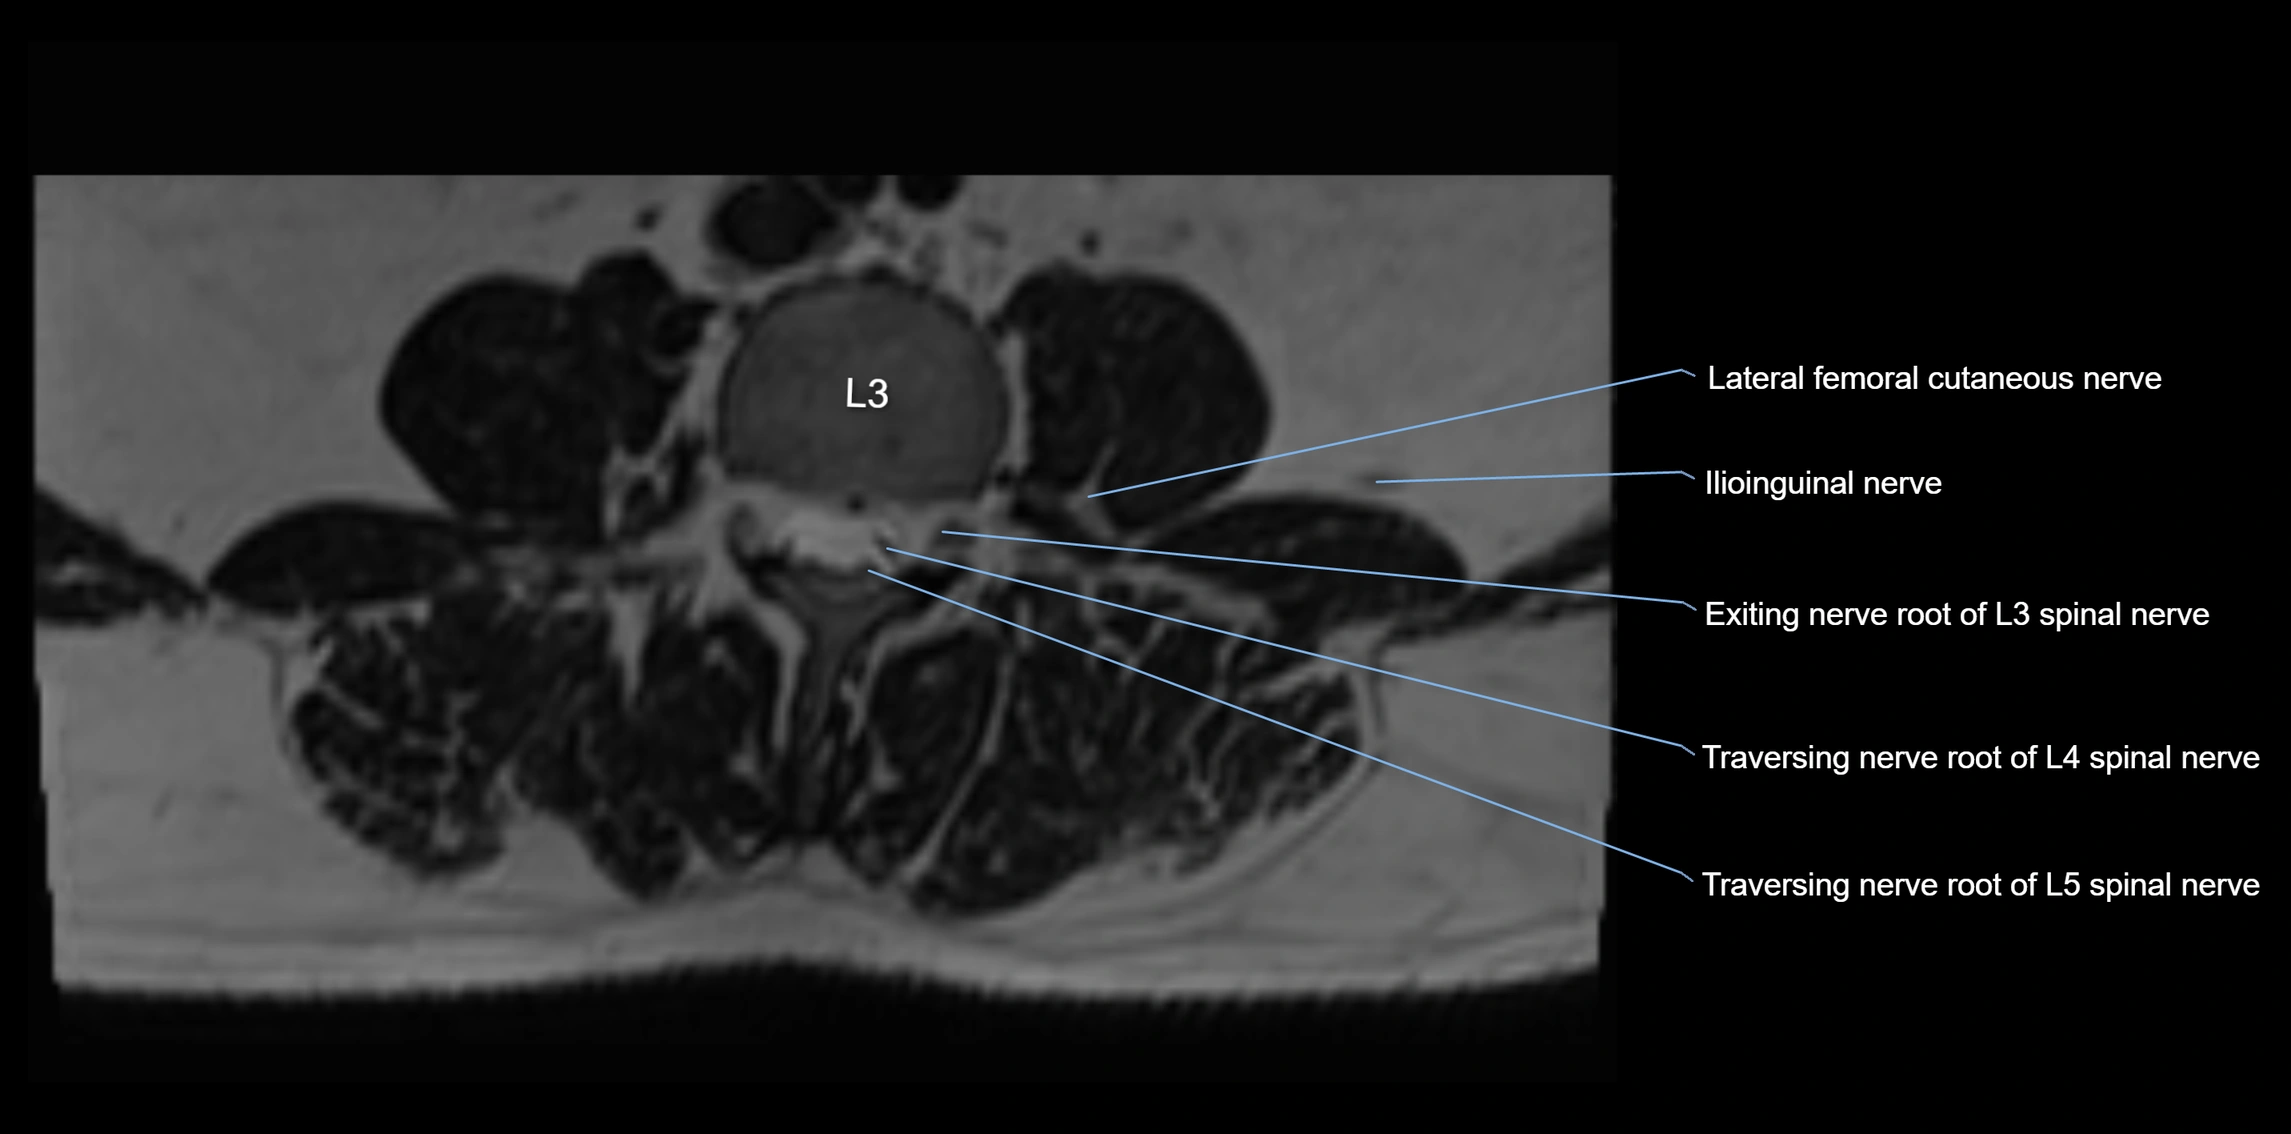

MRI Appearance

T1-weighted images:

• Nerve appears as a very thin low-to-intermediate signal intensity structure

• Surrounded by bright fat, aiding visualization

T2-weighted images:

• Nerve shows intermediate to mildly hyperintense signal compared to muscle

• Pathological involvement appears brighter

STIR (Short Tau Inversion Recovery):

• Normal nerve appears dark

• Inflamed or entrapped nerve appears bright hyperintense

T1 Fat-Sat Post-Contrast:

• Normal nerve enhances minimally

• Pathologic nerve (neuritis, entrapment, tumor infiltration) shows focal or diffuse enhancement

3D T2 SPACE / CISS:

• Nerve appears intermediate to mildly hyperintense compared to muscle

• Surrounded by bright fat or CSF, improving visualization

• Best sequence for mapping small pelvic nerves such as the anococcygeal

MRI image

image